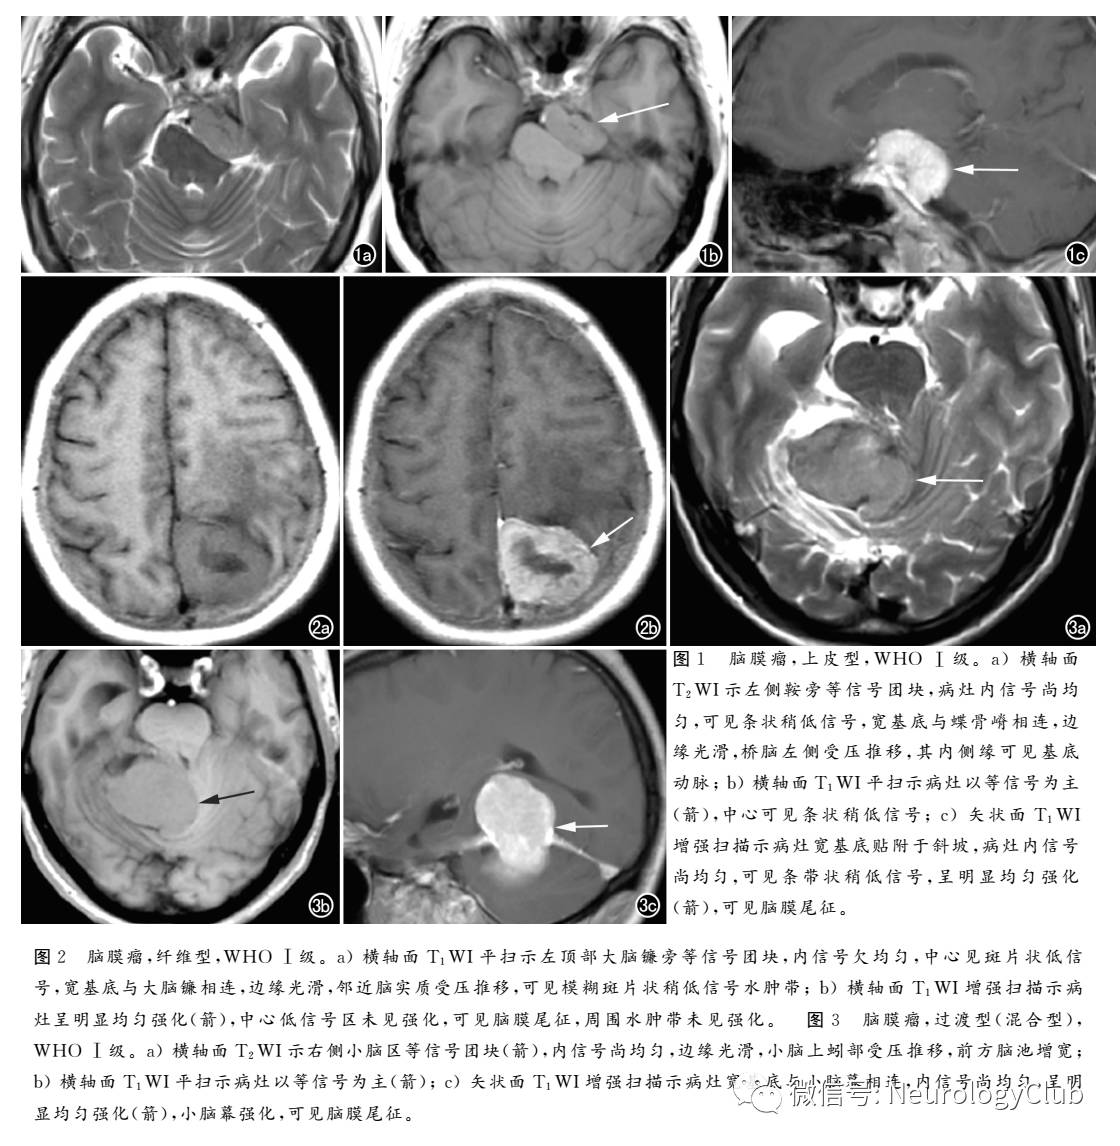

上皮型为最常见的良性脑膜瘤类型,肿瘤细胞与正常蛛网膜内皮细胞十分相似,WHO I级。绝大多数肿瘤形态规整,边缘光滑,边界清晰,肿瘤内信号较均匀,瘤周水肿少见。T1WI、T2WI均表现为等或稍高信号,增强扫描呈明显均匀强化(图1)。肿瘤内部信号均匀,坏死、囊变少见,与肿瘤由上皮细胞组成、间质含水较多、质地稀软有关。

纤维型常见的脑膜瘤类型,由长梭形的纤维状细胞组成,肿瘤组织中富含纤维成分,WHO I级MRI多表现为T1WI呈等或略低信号,T2WI呈等或略高信号,中央可见极低信号(图2)。包膜多完整,由于瘤体内胶原纤维发生玻璃样变及钙化,使其自由水含量减少、间质成分增多,从而造成其T2WI信号较低。瘤周水肿少见且范围局限;增强扫描表现为中、重度强化

过渡型有任何两种或两种以上不同病理类型的脑膜瘤,WHO I级;病理成分较多,玻璃样变性、坏死、钙化等较多见。故MRI信号各异、混杂、不均匀(图3);肿瘤往往较大,常呈分叶状,瘤周水肿轻微